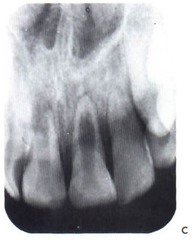

internal resorption

-round to ovoid radiolucency in the central part of the tooth -chronic inflammation -may see pinkish hue to crown if it is involved